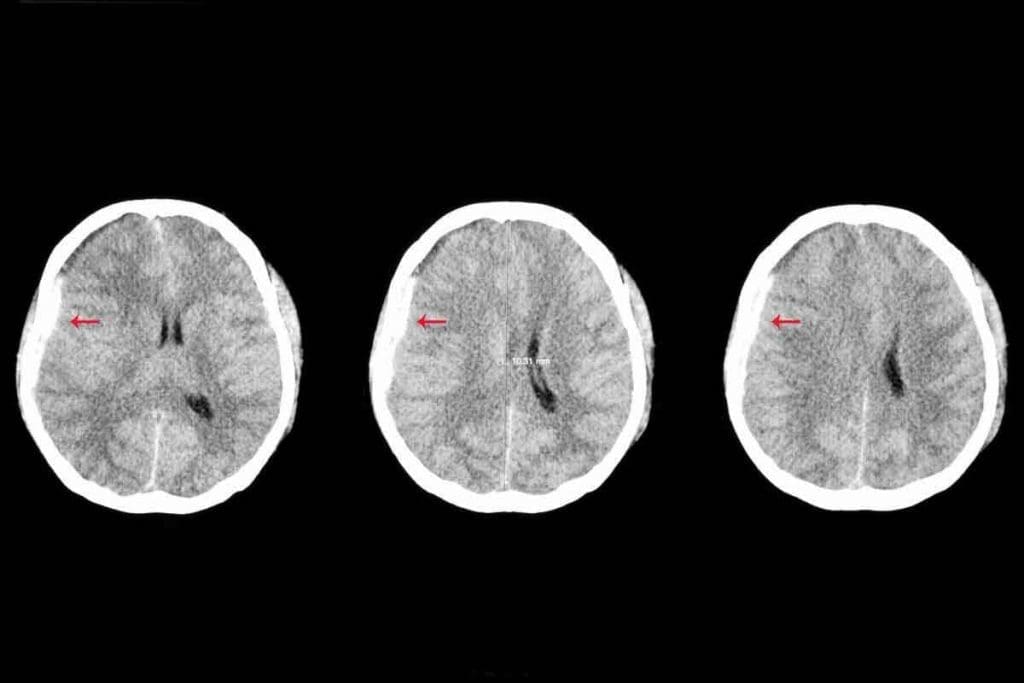

Brain Tumor CT Scan: What Doctors Look For

On a CT scan, tumors show up as masses with odd shapes. They might look hypodense (darker) or hyperdense (lighter) than the brain. Their edges are often irregular.

Doctors check the tumor’s size, where it is, and if it’s pushing on brain structures. They also look for signs like calcifications or bleeding inside the tumor.

Interpreting Scan Results: Density, Borders, and Enhancement

When looking at scans, doctors focus on a few things. They check the tumor’s density, shape, and how it reacts to contrast. The density can tell them what the tumor is made of.

- The tumor’s shape can hint at its aggressiveness. Tumors with clear edges might be less serious, while those with fuzzy edges could be more aggressive.

- How the tumor reacts to contrast can also give clues. This can tell doctors about the tumor’s blood flow and how serious it is.